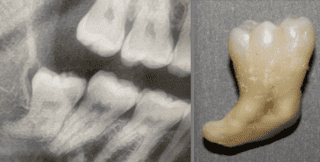

Superb extraction skills

Abs was in for a day full of complex extractions today.... He is known for being so skilled and kind... we love a good Oral Surgery day. We accept referrals from 54 local practices - if you want treatment by a calm clinician - he is your GO TO!